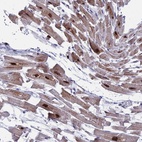

Immunohistochemical staining of human heart muscle shows cytoplasmic positivity in myocytes.